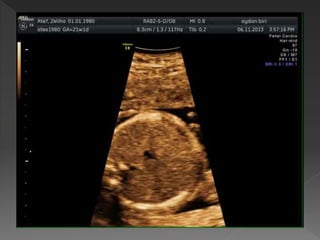

 Diyaframın hemen üzerinde toraksın

tranvers kesiti ile elde edilir

 Fetusun oryantasyonuna bağlı

apikal, lateral ya da ters apikal

görüntü alabilir

 Tümü analiz yapmak için uygundur

 Fetal omurga aşağıda olduğunda

ideal olarak görüntülenir